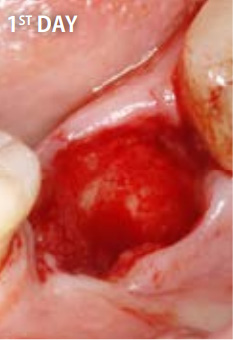

●通常の治療

抜歯直後

15日後

一方、自然治癒を待つ場合には、穴が完全にふさがるまでに数ヶ月かかります。その間にドライソケット(抜歯窩治療不全)になったり、食べ物が詰まるなど、痛みや悪臭を伴うこともあります。